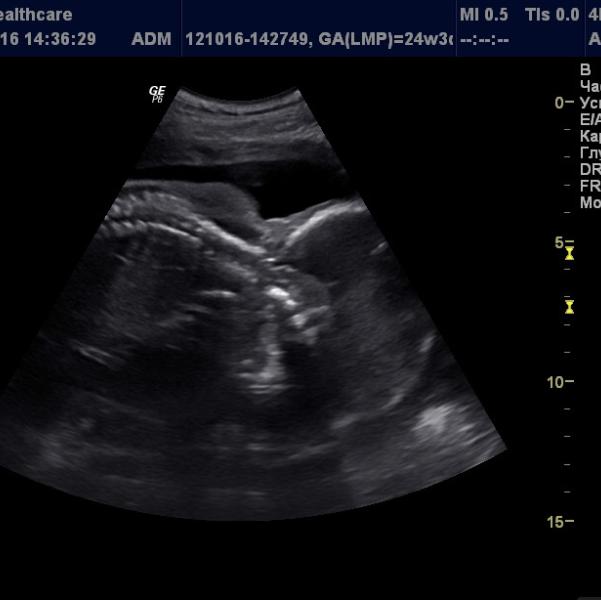

Девочки что это?)))) не могу понять то от руками лицо закрывает. Кто хорошо разбирается подскажите. И ещё в каментах фото

У вас мальчик?😄😊 на первой фото в комментариях похоже на то))

На первой фотке похож на писюн) у меня у сына такая фотка была